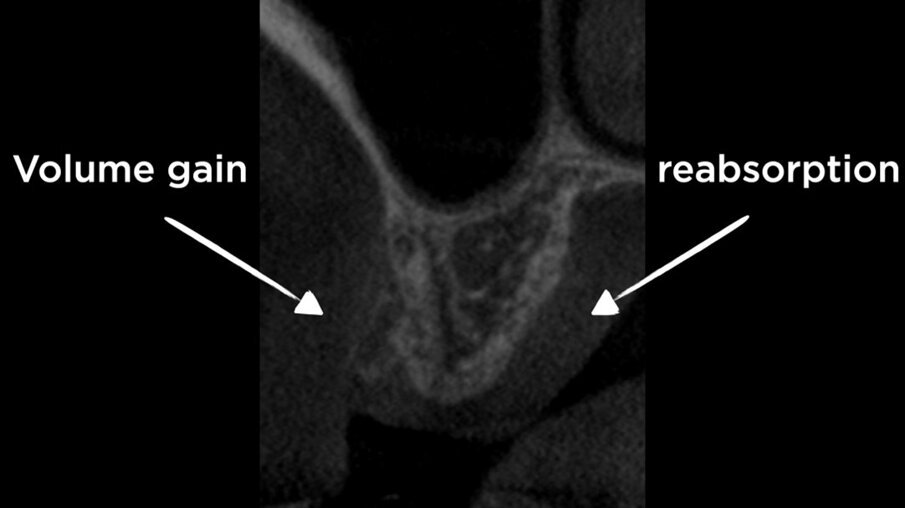

La CBCT dopo 4 mesi ha mostrato il mantenimento della corticale vestibolare (Figg. 7a, 7b), e anche un aumento della dimensione bucco-linguale (Fig. 8). Sul lato palatale, dove il sito è guarito naturalmente, la parete palatale ha subito un normale rimodellamento. Le immagini CBCT mostrano chiaramente la capacità della lamina corticale di inibire il riassorbimento della corticale buccale e di sostituirla o sostenerla. Ciò suggerirebbe che la lamina potrebbe essere utilizzata al posto di una membrana D-PTFE per ottenere un risultato ancora migliore rispetto alla classica tecnica di inibizione periostale, considerando anche che la lamina si integra nel sito8, 9 e non richiede una procedura di rientro. La guarigione è avvenuta senza complicazioni e il volume osseo creato era sufficiente per posizionare un impianto standard da 4,1 mm (Figg. 9, 10).

Figg. 7a, 7b - CBCT dopo Inibizione Periostale Modificata.